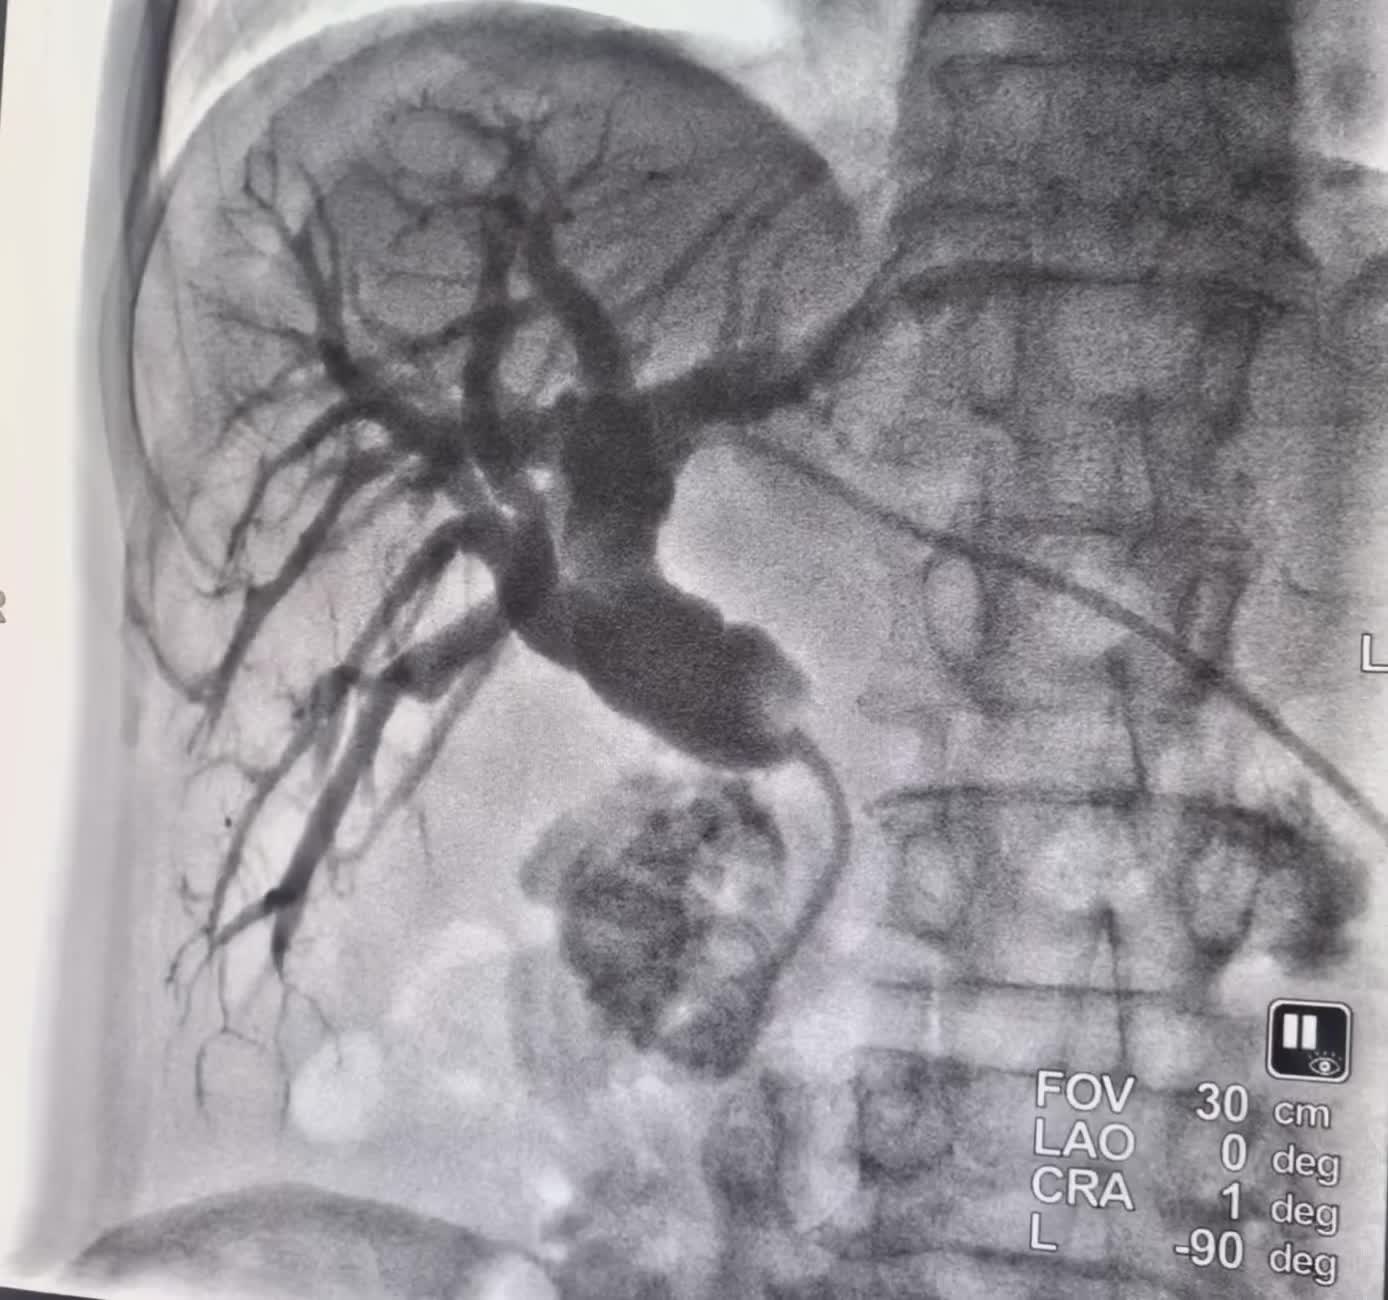

一例胰头癌压迫胆管引起的梗阻性黄胆伴胆管 一例胰头癌压迫胆管引起的梗阻性黄胆伴胆管感染,经过不断艰辛的努力打通梗阻的胆管,置入胆道内外引流导管。快速退黄控制感染最有效的方法。